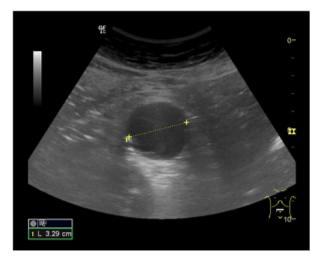

Informe: Hígado de tamaño y ecogenicidad normal. Vesícula distendida con 2 litiasis de 2 x 3 mm en su interior. Páncreas y bazo de ecoestructura normal. Ambos riñones de tamaño, ecogenicidad en rango, diferenciación corticosinusal. Vena porta, cava inferior y aorta en el área del lóbulo hepático izquierdo de calibre normal. Aneurisma de aorta abdominal descendente hasta su bifurcación de ambas iliacas de 3.29 cm en su eje trasversal con engrosamiento de pared posterior.

• Aneurisma de aorta abdominal.

Desde el seguimiento realizado por el Servicio de Cirugía vascular se observa un crecimiento paulatino de 0,6 cm en 6 meses por lo que se decide intervenir quirúrgicamente.